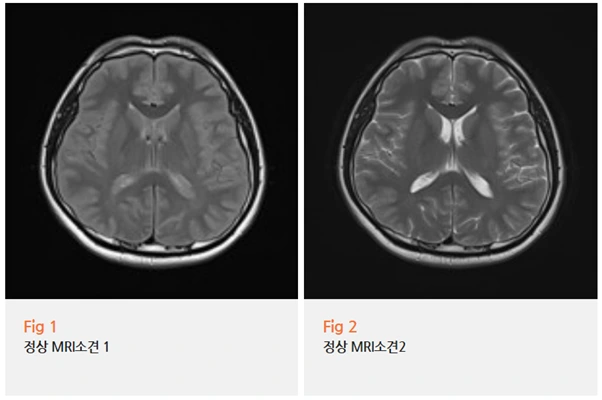

뇌 MRI까지 찍어보셨다고 했습니다.

결과는?

전부 정상.

이상 소견 없음.

이런 경우 환자분들이 제일 답답해하세요 ㅠㅠ

아픈 건 분명한데, 검사상으론 아무 이상이 없다고 하니까요.